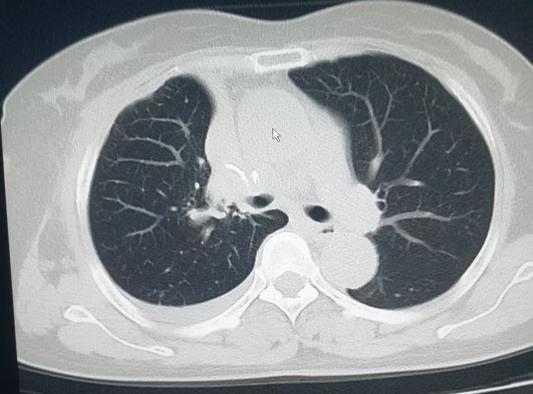

随后,心胸外科医生对王女士的病情进行了会诊,王女士也在完成耳鼻咽喉科的治疗后,欣然接受了医生的建议,果断选择胸腔镜下结节切除术。术后病理检查结果证实,病灶为早期浸润型腺癌。幸运的是,由于发现及时,王女士术后恢复良好,顺利出院。劫后余生的王女士,对医院的感激之情溢于言表,她感慨道:“真的太感谢医院了,不仅治好了我的病,更让我见识到现代影像诊断在AI智能加持下的强大力量,是它帮我及时发现了隐藏的‘健康杀手’!”

(手术后)